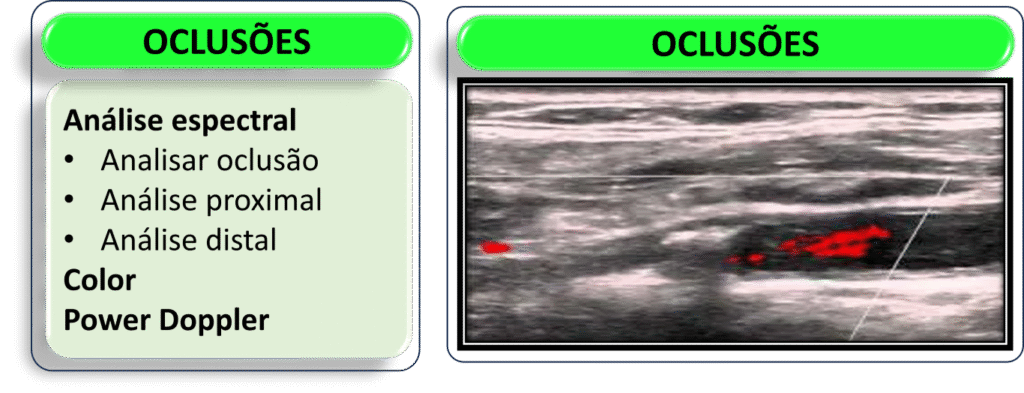

Oclusão ACI

Ausência de espessamento parietal e tortuosidades significativas, com a presença de placas ateromatosas hiperecogênicas ocupando toda a luz do vaso, localizadas em terço proximal, e sem sinais de fluxo ao Doppler espectral.